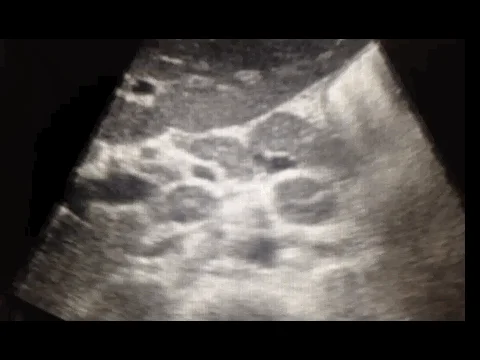

A 35 male year old patient in Malawi presents with 3 months of chronic night sweats, low grade fevers and weight loss. He has a history of HIV and on ART’s. His TB sputum smear test is negative and a chest x-ray is negative. You decide to perform a FASH exam. The following image is a transabdominal ultrasound, transverse of the midline.

What is your diagnosis?

Answer: B. Extrapulmonary Tuberculosis. The circular hypoechoic rings with hyperechoic borders and hyperechoic centers are abdominal lymph nodes, a finding present as part of the FASH protocol.

In extrapulmonary tuberculosis (TB), para-aortic lymph nodes can become enlarged due to infection. This is more commonly observed in patients who are immunocompromised, such as those with HIV. Sonographically, these lymph nodes usually appear hypoechoic and rounded due to loss of internal structures caused by caseous necrosis. The lymphadenopathy may be discrete, or nodes might be conglomerated into larger masses .

When using ultrasound to detect these nodes, they are visualized as hypoechoic structures, sometimes appearing to blink as the probe moves, distinguishing them from vessels that have consistent flow patterns. Enlarged nodes are typically over 1.5 cm in size in adults .

The presence of enlarged para-aortic lymph nodes in ultrasound, especially in the context of other findings such as splenic microabscesses, supports a diagnosis of abdominal TB in suspected cases.